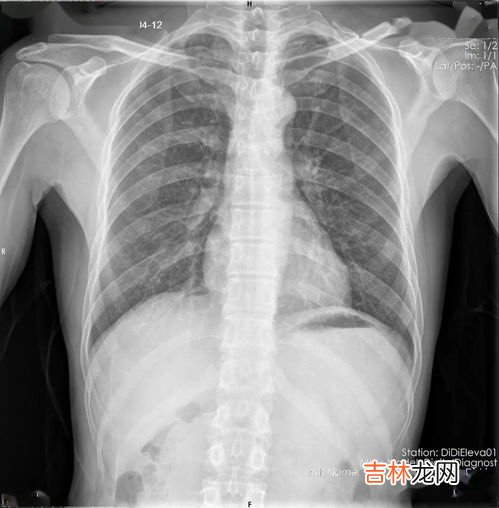

文章插图